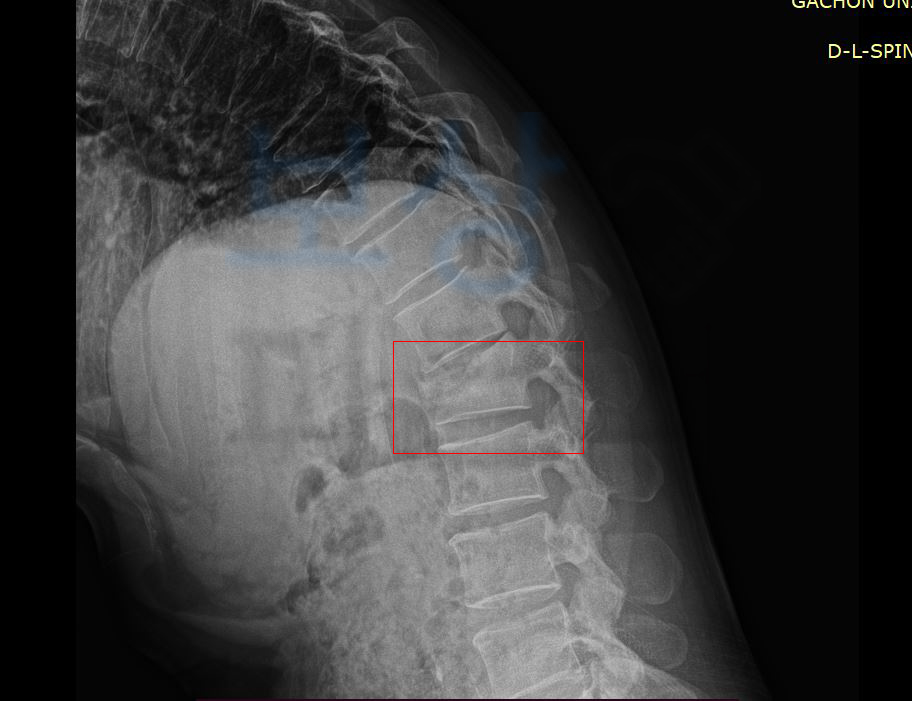

L1 부위의 골절 S3202 즉 요추1번 척추압박골절 진단을 받아 최소 12주간의 요양이 필요하셨는데요, 위 처럼 요추압박골절은 추락하거나 넘어지거나 부딪히는 외부의 강한 충격에 의해

척추에서도 움직임이 많은 요추와 흉추가 만나는 흉추12번이나 요추1번과 같은 부위에 흔히 발생합니다. 흉추와 요추가 만나는 부분은 흉추의 후만과 요추의 전만이 교차하기에 충격이 고스란히 집중되고 대부분 척추의 앞기둥 부위가 골절됩니다.